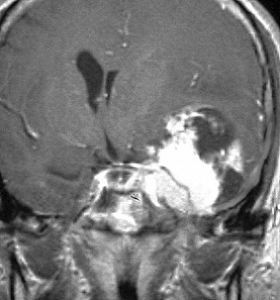

典型的な髄膜腫

この髄膜腫は中程度の大きさのものです。円蓋部髄膜種という最も多い最も手術の簡単なタイプです。麻痺や失語症やてんかんなどの症状はありません。とても美しくて若い女性の髄膜腫でしたが,子供に遺伝はしませんし,癌などと違ってタバコなどこれといった原因がなくて発生するものです。

MRIでの髄膜腫の見え方は撮影の仕方によっていろいろです。左からT1強調画像,T2強調画像,フレア画像といいます。腫瘍の横に小さく白い領域がありますが,これは脳の腫れた部分で脳浮腫といいます。髄膜腫があると周囲に脳浮腫が生じることがあります。

最も見やすいのが,ガドリニウム造影剤を注射して撮影するものです。一般的に髄膜腫は造影剤で白く映し出されます。この腫瘍は左脳側にあります。MRIの軸面という輪切りの写真では左右が逆になりますから注意してください。脳を下から見た図になっています。MRIはいろいろな方向から腫瘍を見ることができますが,右は冠状断という正面から見た図です。よく見ると腫瘍の上と下のはじっこに線状に糸を引いたように造影される部分があります。これをテールサイン(しっぽのサイン)といいます。腫瘍が硬膜に沿って延びている可能性があることを示しています。